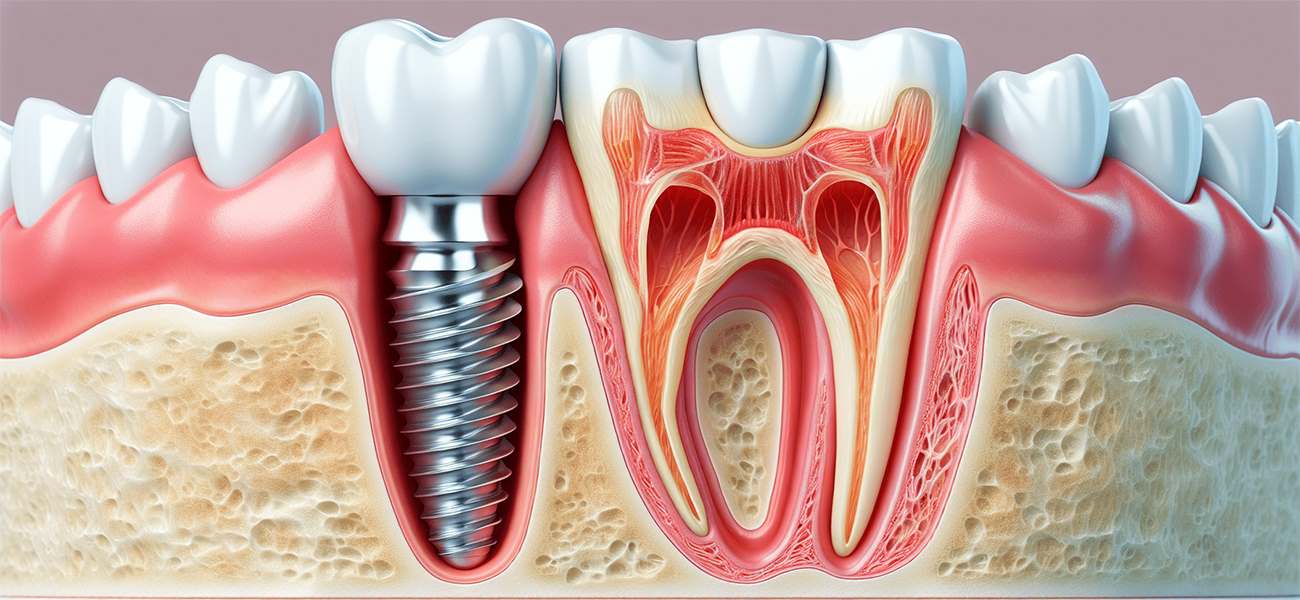

ایمپلنت دندان یکی از پیشرفتهترین و موثرترین روشهای درمانی در دندانپزشکی است که به بیماران این امکان را میدهد تا دندانهای از دست رفته خود را با دندانهای مصنوعی جایگزین کنند. انتخاب یک جراح ایمپلنت ماهر و با تجربه، به خصوص در مناطقی مانند سیدخندان، برای موفقیت این درمان بسیار حیاتی است. در این مقاله، به بررسی ویژگیها و خدمات دندانپزشکی دکتر مهسا فربد، یکی از بهترین جراحان ایمپلنت دندان در سیدخندان، خواهیم پرداخت.( دکتر مهسا فربد فلوشیپ ایمپلنت از فرانسه, بهترین جراح ایمپلنت دندان )

- انجام عمل ایمپلنت

عمل ایمپلنت یکی از مراحل حساس درمان است که نیاز به دقت و مهارت بالایی دارد. دکتر فربد با استفاده از تکنیکهای پیشرفته، عمل ایمپلنت را با کمترین عوارض جانبی انجام میدهد.